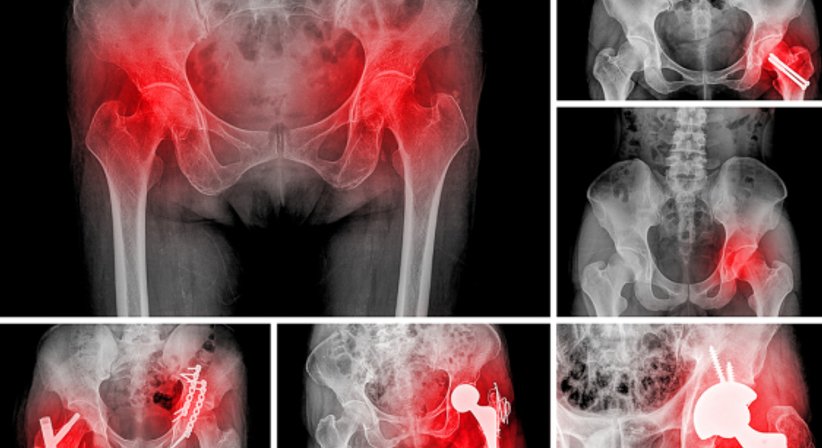

Bei Patienten mit massiver Arthrose des Hüftgelenks, bei welchen konservative Therapien nicht mehr wirksam sind, ist die Implantation einer Hüftprothese sinnvoll, um die Schmerzen im Bereich der Hüfte dauerhaft zu beseitigen und die Mobilität und folglich auch die Lebensqualität zu verbessern.

Bei einer Hüftprothese handelt es sich um eine implantierte Prothese, die das Hüftgelenk zur Gänze ersetzt (künstliche Hüfte). Gemeinsam mit der Knieprothese zählt die Hüftprothese zu den am häufigsten implantierten Gelenkendoprothesen überhaupt. Für die Implantation stehen unterschiedliche Hüftprothesen und operative Vorgehensweisen zur Wahl. Bei den für eine Hüftgelenksprothese verwendeten Materialien handelt es sich um Metalle, Keramik und Polyethylen (Metall-Metall-Gleitpaarung, Keramik-Keramik-Gleitpaarung, Metall-Polyethylen-Gleitpaarung, Keramik-Polyethylen-Gleitpaarung). Welche Prothese am besten geeignet ist hängt ganz von der individuellen Anatomie und den individuellen Bedürfnissen des Patienten ab und wird nach einer exakten Diagnose ausführlich besprochen.